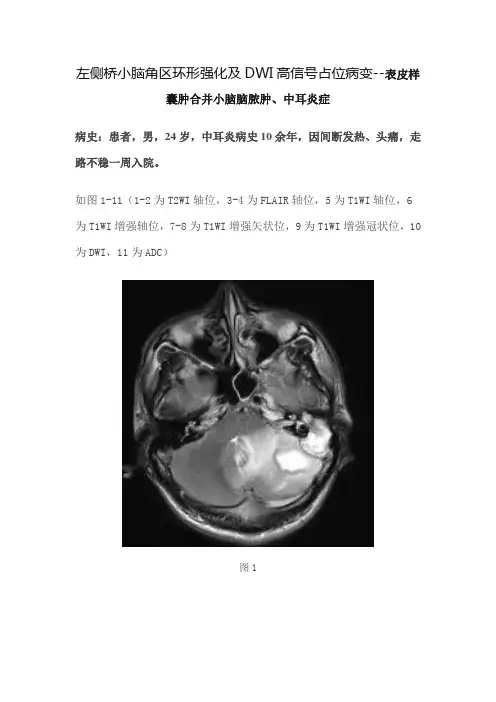

左侧桥小脑角区环形强化及DWI高信号占位病变--表皮样囊肿合并小脑脑脓肿、中耳炎症病史:患者,男,24岁,中耳炎病史10余年,因间断发热、头痛,走路不稳一周入院。

如图1-11(1-2为T2WI轴位,3-4为FLAIR轴位,5为T1WI轴位,6为T1WI增强轴位,7-8为T1WI增强矢状位,9为T1WI增强冠状位,10为DWI,11为ADC)图1图2图3图4图5图6图7图8图9图10图11基础影像解剖:图12图13图12-13为所示病例同层面轴位及矢状位正常T2WI图片,黄色箭头所示为正常耳蜗长T2信号,棕色箭头所示为正常听神经稍长T2信号,MRI图像中骨质因不含自由水呈低信号,无法显示内听道骨质结构,蓝色箭头所示为桥小脑角池长T2信号,其内无异常信号影,其内线形低信号为听神经及小血管流空信号影。

白色箭头所示颞骨乳突内气体及骨质均呈低信号。

图1图2图3图4图5图6图7图8图9图10图11图1-11所示左侧内听道未见异常(绿色箭头)。

左侧颞骨乳突骨质破坏(黄色箭头),左侧颞部乳突可见类圆形异常信号影,边界清晰,呈长T1长T2信号,FLAIR呈等高信号,信号欠均匀,增强无强化,DWI 高信号,ADC低信号,提示弥散受限。

左侧桥小脑角区可见多发类圆形异常信号影(棕色箭头),呈长T1、长T2信号,FLAIR呈等高信号,内部信号不均,病灶似见分隔及包膜,增强呈子母灶环形明显强化,内外壁光滑,临近硬脑膜强化,DWI呈高信号,ADC低信号,提示弥散受限。

病灶周围见大片水肿信号影(蓝色箭头)。

黄色箭头:左侧颞骨乳突区骨质破坏,可见类圆形异常信号影,呈长T1长T2信号,信号不均,增强无强化,DWI高信号,ADC低信号。

棕色箭头:左侧桥小脑角区可见多发类圆形异常信号影,呈T1长T2信号,信号欠均匀,其内似见分隔,增强呈子母灶环形明显强化,内外壁光滑,临近硬脑膜强化。

DWI呈高信号,ADC低信号。

蓝色信号:病灶周围见大片状长T1长T2信号,FLAIR呈高信号,DWI 呈低信号,ADC呈高信号,提示血管源性水肿。